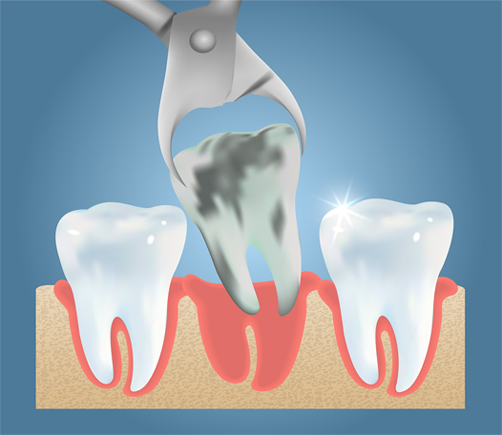

When a tooth is severely infected, fractured, or causing intense pain, we provide gentle extractions to relieve symptoms and prevent complications.